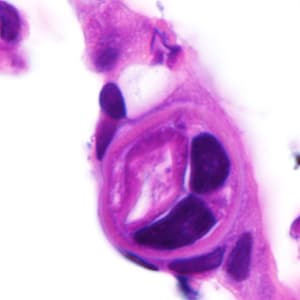

A 25-year-old male was hospitalized for Crohn’s exacerbation, duodenal outlet obstruction, and regional enteritis. He indicated that he has not had recent travel abroad. The patient underwent a gastroenterostomy and duodenal biopsy specimens revealed acute and chronic inflammation with crypt abscesses, focal ulceration, and reactive epithelial changes. Granulomata, epithelial dysplasia, and fibrosis were lacking. The attending pathologist also noted suspect parasitic organisms and the slides were sent to the state health department, which in turn forwarded them to the CDC-DPDx for diagnostic assistance. Figures A–F show what was observed on the slides received for testing. Figure A was taken at 100x magnification; Figures B–D at 400x magnification; and Figures E and F at 1000x magnification with oil. What is your diagnosis? Based on what criteria?

Figure B